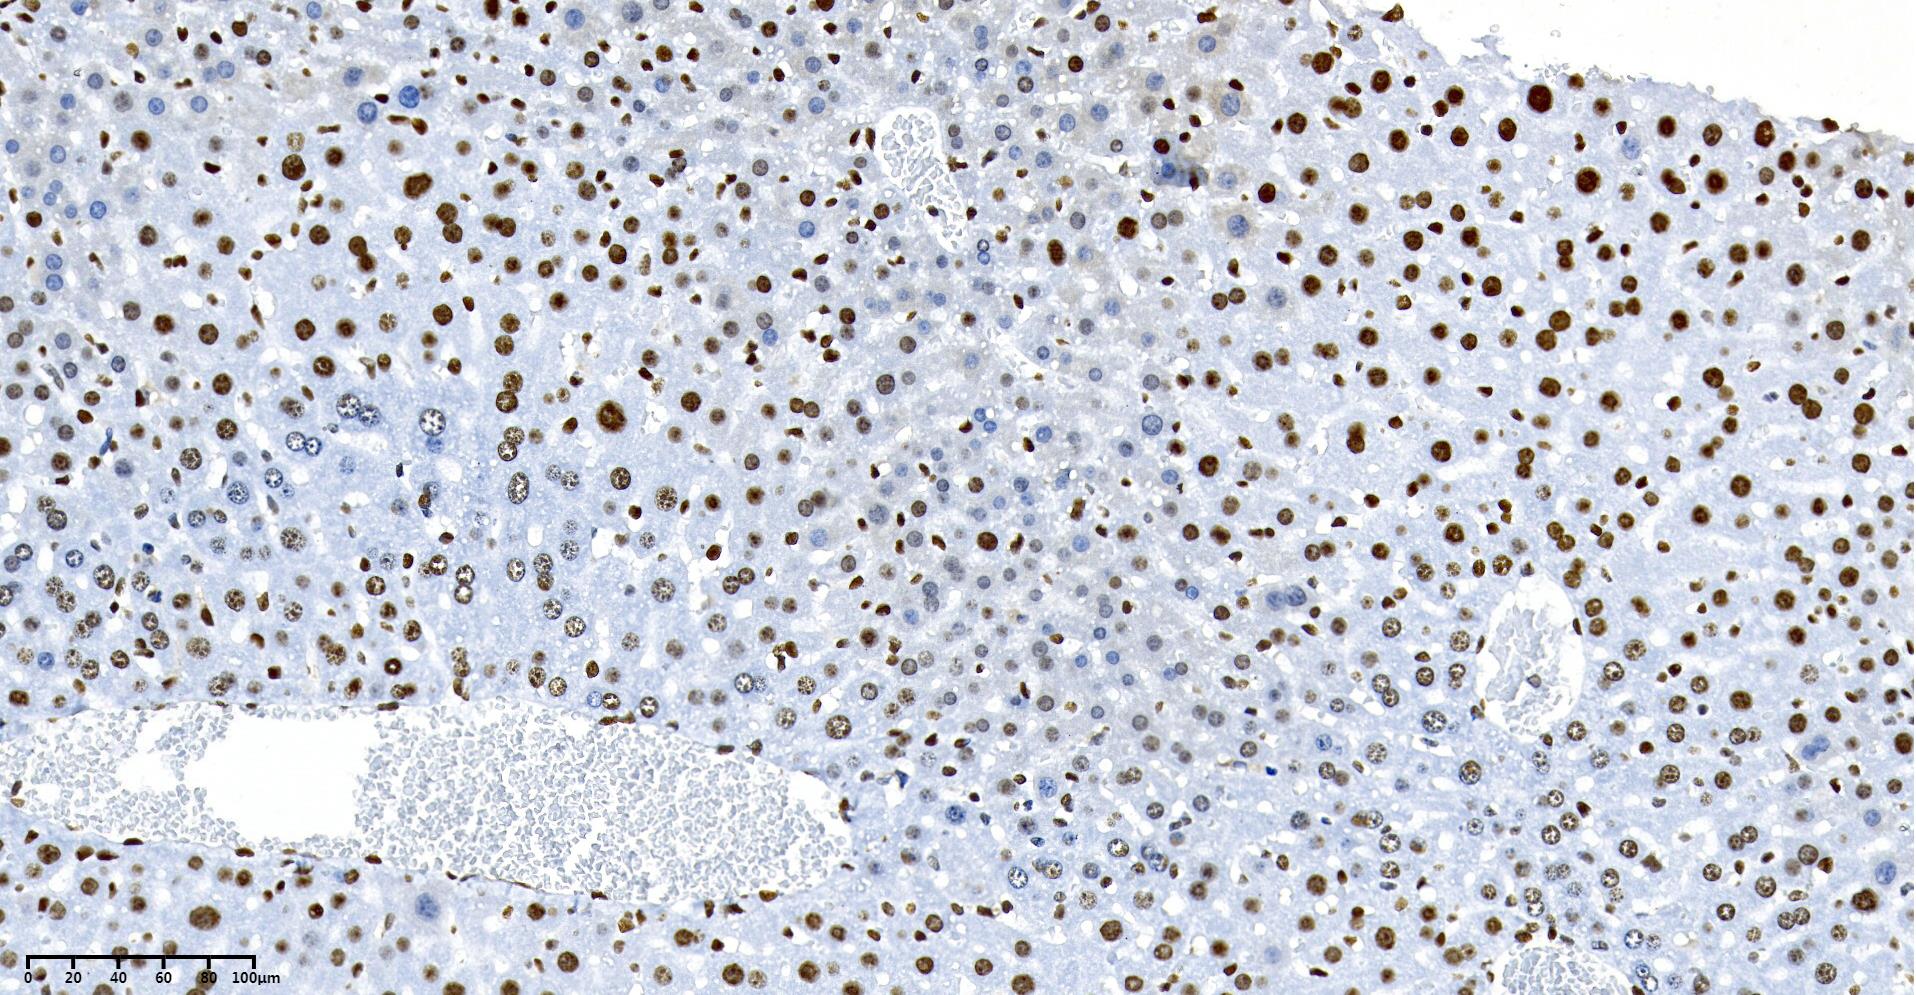

| Immunohistochemistry |

Mouse_liver